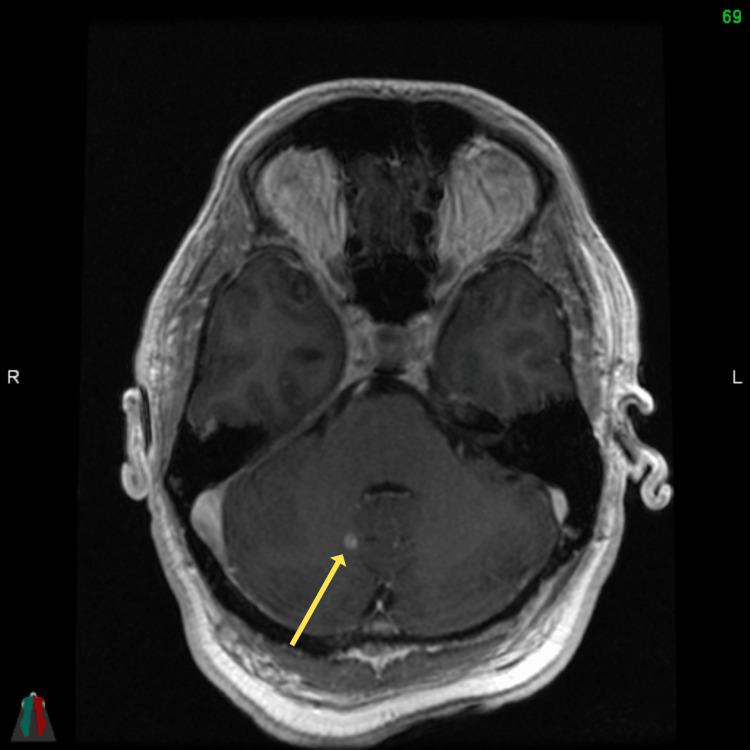

一例非小细胞肺癌所致MRI阴性的柔脑膜疾病病例

A Case of MRI-Negative Leptomeningeal Disease From Non-small Cell Lung Cancer.

Leptomeningeal disease (LMD) is a rare complication of advanced non-small cell lung cancer (NSCLC), associated with a poor prognosis. We report the case of a 55-year-old man, who presented with a metastatic NSCLC with limited brain and abdominal metastases. He was treated with both chemoimmunotherapy and stereotactic radiotherapy (SRT) to the brain. Despite treatment, the patient experienced progressive neurological symptoms not in keeping with the extent of disease seen on imaging of the brain. Due to this incongruence between symptoms and radiologic findings, he underwent a lumbar puncture, which had positive cytology for LMD. He had a rapid progression of symptoms and died six days after the discovery of LMD. We review the available literature regarding the prevalence of MRI-negative LMD from a solid primary malignancy.

摘要

软脑膜疾病(LMD)是晚期非小细胞肺癌(NSCLC)的一种罕见并发症,预后较差。我们报告了一例55岁男性病例,该患者患有转移性NSCLC,脑和腹部转移灶有限。他接受了化疗免疫治疗和脑部立体定向放射治疗(SRT)。尽管进行了治疗,但患者仍出现了与脑部影像学所见疾病范围不符的进行性神经症状。由于症状与放射学检查结果不一致,他接受了腰椎穿刺,脑脊液细胞学检查显示LMD呈阳性。他的症状迅速进展,在发现LMD后六天死亡。我们回顾了有关实体原发性恶性肿瘤中MRI阴性LMD患病率的现有文献。